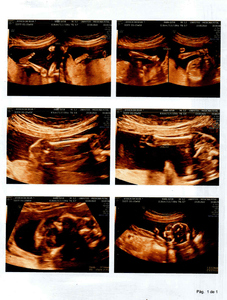

Olá amigos e amigas, eu Laidson Saturnino Souza Santos, descobri que minha filha, com idade gestacional de 21 semanas e 6 dias, foi diagnosticada com MIELOMELINGOCELE SACRAL, ESPINHA BÍFIDA OU ESPINHA ABERTA, no dia 13/09/2022, por meio de uma ultrassonografia morfológica. Ela possui uma MALFORMAÇÃO NA COLUNA. Em decorrência disto provavelmente nascerá com ANOMALIAS ESTRUTURAIS, DOENÇAS GÊNICAS, RETARDO MENTAL, CROMOSSOMOPATIAS (SINDROME DE DOWN), entre outros problemas. A única forma de tentar reverter esse problema seria uma cirurgia intrauterina, ou seja, os médicos farão uma cesárea, irão abrir o útero da mãe, chegar até meu filho, onde irão fechar a sua coluna, q está aberta. Feito isto suas chances de nascer perfeito São grandes, claro que os médicos não descartam a hipótese de haver sequelas, mas acreditamos na cura total. Se a mãe não se submeter a esse procedimento, assim q ela nascer irá pra cirurgia para fechar a coluna, mas já será tarde demais e consequentemente ficará sem andar entre outras complicações e por fim será uma menina especial pro resto da vida. Estamos aqui correndo contra o tempo, pois o prazo será até a 26ª semana, ou seja, temos 4 semanas para organizar tudo, e levantar o dinheiro. Não sabemos ao exato o quanto custa essa cirurgia, mas passa de $ 20,000 DÓLARES, aqui no Brasil. Onde moramos, Bahia, este procedimento não é realizado, só em São Paulo ou Rio de Janeiro. Então abandonaremos tudo aqui, família, amigos, ...  para tentar dar um futuro melhor para a LIZ. Estamos tentando os órgãos públicos para obtermos a cirurgia através do SUS (Sistema Único de Saúde). Mas é difícil e não temos como esperar. Então criamos uma conta para levantarmos a quantia suficiente e assim poder realizá-la. Peço que quem tiver interesse em ajudar repasse esta mensagem aos seus amigos, para juntos salvarmos a vida da minha menina.